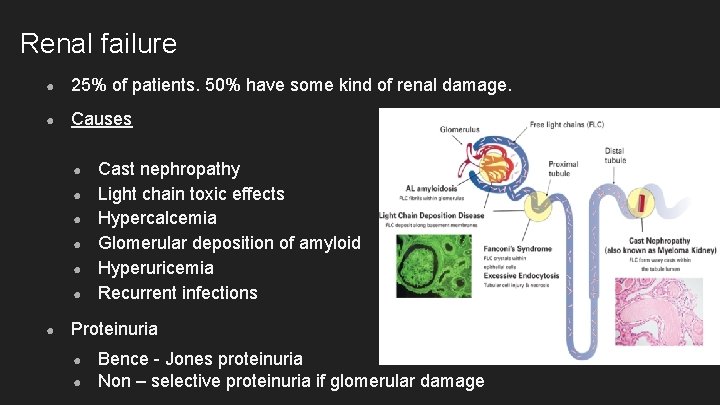

Renal failure ● 25% of patients. 50% have some kind of renal damage. ● Causes ● ● ● ● Cast nephropathy Light chain toxic effects Hypercalcemia Glomerular deposition of amyloid Hyperuricemia Recurrent infections Proteinuria ● ● Bence - Jones proteinuria Non – selective proteinuria if glomerular damage